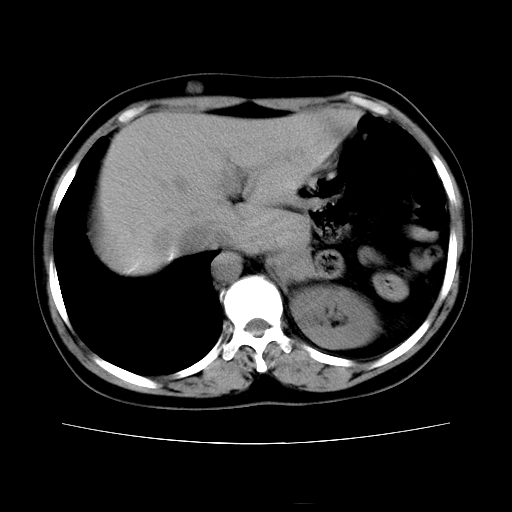

女45y多次(7次)碎石,结果不理想!曾碎石后尿出小碎石,仍腰痛,要求ct,其它不详.本人更倾向于钙化斑!无肾实质破坏,积水等提示集合系统无梗阻.另外腹腔多处钙化.是否结核后改变!谢谢赐教!

1)双肾结石。2)脾脏钙化灶。3)腹膜后多发淋巴结钙化。

尿路结石与腹部淋巴结钙化共存,建议v尿路造影检查,免得钙化灶冤枉为结石受罚。

考虑双肾结石,肾脏实质无破坏表现,没有结核病史,不考虑肾结核,